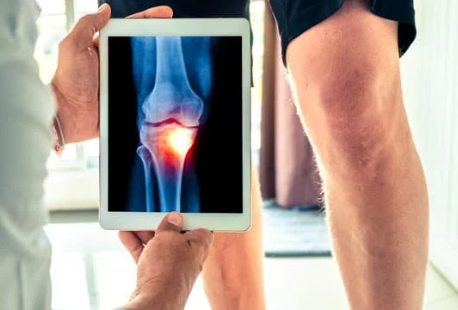

무릎 관절 통증의 치료 방법

무릎 통증을 완화하고 치료하기 위해서는 다음과 같은 방법이 있습니다.

- 휴식: 통증이 느껴지는 경우, 무릎을 쉬게 하고 부하를 줄이는 것이 중요합니다. 필요하다면 일시적으로 운동을 중단하세요.

- 얼음찜질: 통증과 부기를 줄이기 위해 얼음찜질을 이용하세요. 15-20분간 얼음팩을 적용해 부위를 시원하게 해주는 것이 좋습니다.

- 약물 요법: 비스테로이드 항염증제(NSAIDs)와 같은 약물은 통증 완화에 도움을 줄 수 있습니다. 의사와 상담 후 복용하세요.

- 물리치료: 전문 물리치료사의 도움을 받아 운동 범위를 늘리고 무릎 관절을 강화하는 운동을 진행하는 것이 좋습니다.

- 수술: 심한 경우에는 관절경 수술이나 인공관절 수술 등의 선택지가 있을 수 있습니다. 의료 전문가와의 상담이 필수입니다.